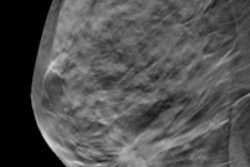

Breast cancer screening with digital breast tomosynthesis (DBT) benefits women over 65, with fewer false positives and no statistically significant difference in sensitivity or cancer detection rate, according to a new study published online April 2 in Radiology.

"In our study evaluating the performance of screening mammography in women aged 65 years and older, we found that integration of digital breast tomosynthesis led to improved screening performance metrics, with a lower abnormal interpretation rate, higher positive predictive value, and higher specificity," the group wrote. "Because the benefits of early cancer detection are maintained and the potential risks of false-positive examinations are lower with DBT in older women, our study supports guidelines recommending that screening decisions be based on individual preferences and health status rather than age alone."

Bahl and colleagues sought to compare the performance of DBT to conventional 2D digital mammography among women 65 and older. They included 30,529 2D screening mammograms from more than 15,000 women (mean age, 72.7 years) and 41,429 DBT screening mammograms from more than 20,000 women (mean age, 72.1 years).

The team found that both 2D and DBT mammography were effective at detecting cancer in this older population, but tomosynthesis had some advantages, such as a lower false-positive rate, a higher positive predictive value (PPV), and higher specificity.